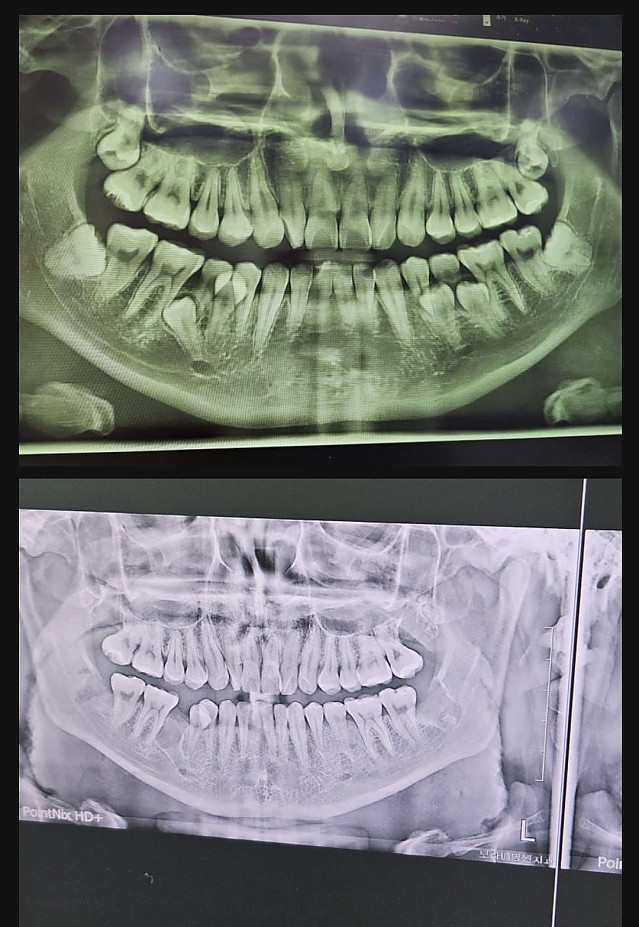

사랑니 갤러리 갤주 작성자 정보 붐붐의민족 작성 작성일 2024.10.18 11:28 컨텐츠 정보 14,030 조회 1 댓글 목록 본문 서울대병원 전신마취 수술로 정상화 완료 관련자료 링크 https://www.kaov.org/bbs/board.php?bo_table=KA_3101&wr_id=5318 539 회 연결 댓글 1 김김바리님의 댓글 김김바리 작성일 2024.10.18 15:27 이게되노... 16 럭키포인트 당첨! 이게되노... 로그인한 회원만 댓글 등록이 가능합니다. 목록